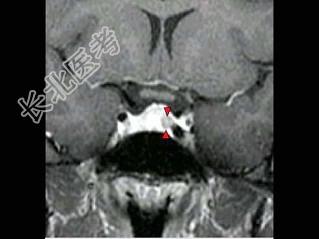

- 单项选择题女,38岁, 头痛、闭经,MRI检查如图, 最可能的诊断是 ( )

D、垂体微腺瘤